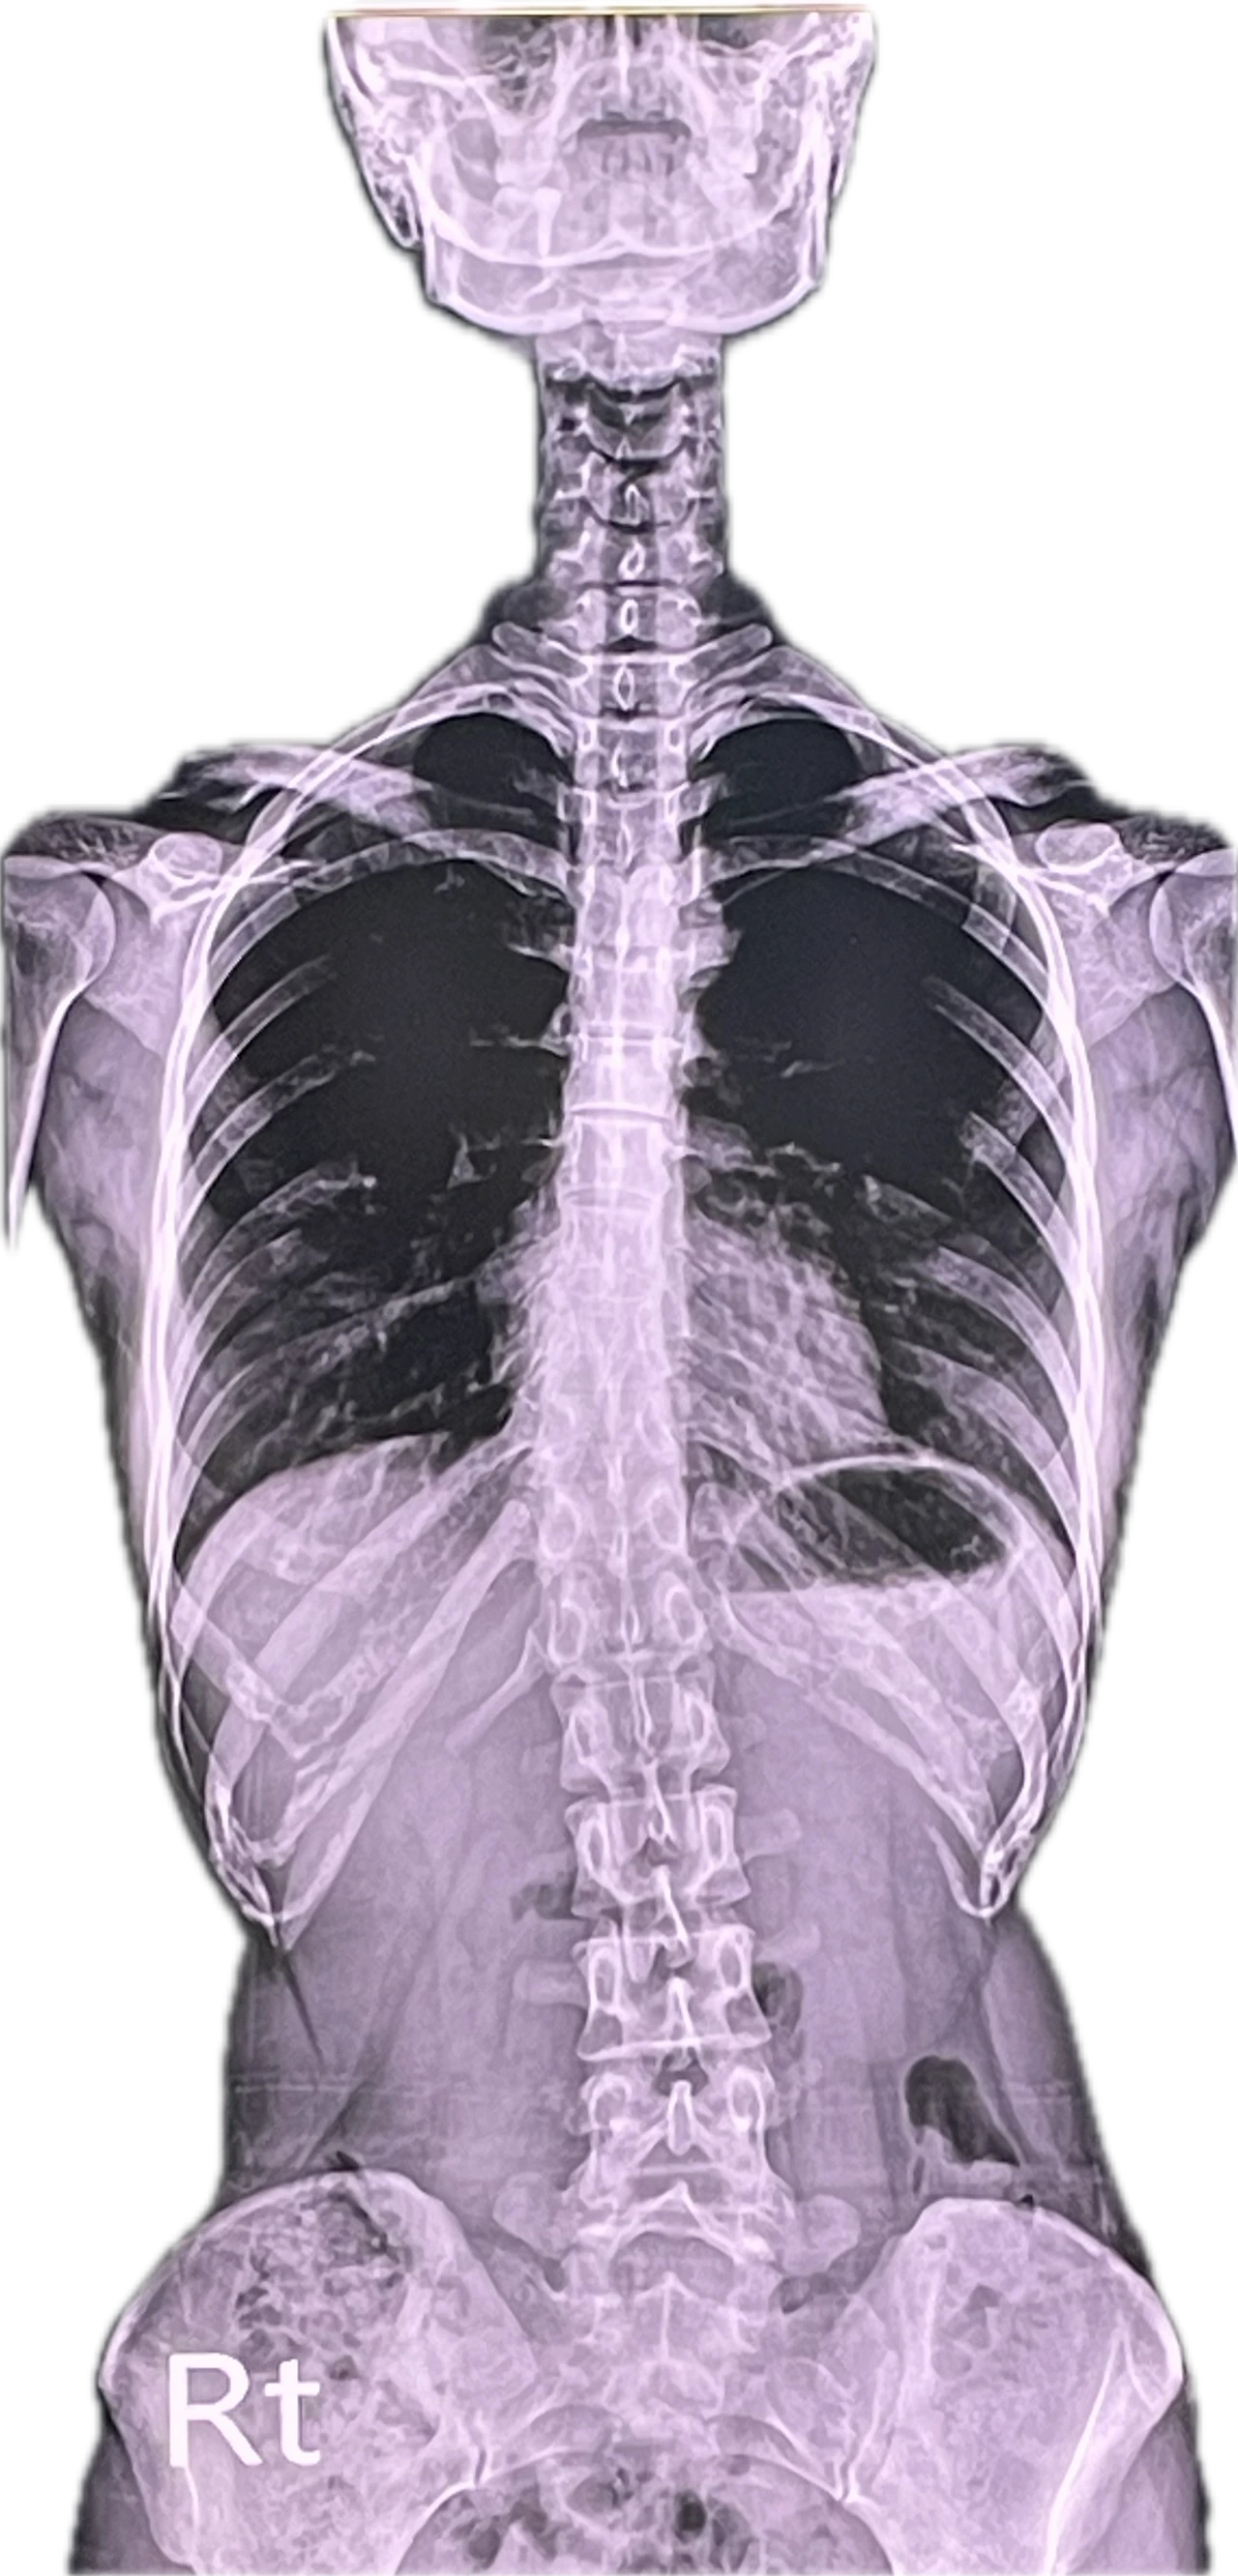

예상외로 사진 상 무릎은 멀쩡하고 척추와 골반이 많이 틀어졌다고 한다.

평소에 왼다리만 반 접어서 의자 위에 가부좌를 틀고 있는 습관이 있어서 골반이 틀어지고 허리도 좀 이상한 것 같다.